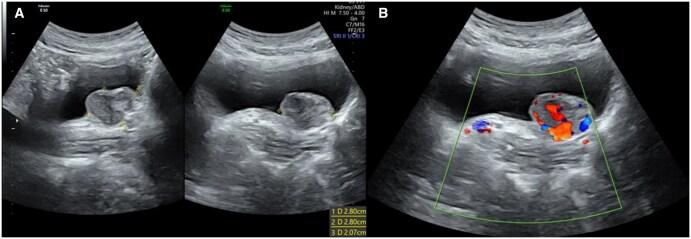

Paragangliomas (PGLs) during pregnancy is an uncommon neuroendocrine tumour that is associated with increased maternal and foetal morbidity and mortality. Furthermore, it is even rarer for these to be located within the urinary bladder, with a prevalence of <0.1% of all bladder tumours. This case report details a 29-year-old female who presented with pre-syncope, headache, and palpitations during voiding. Ultrasound and magnetic resonance imaging of the pelvis revealed a mass in her bladder, and biochemical workup demonstrated elevated plasma normetanephrine levels and a positive clonidine suppression test. Surgical resection and histopathology of the mass were consistent with PGL. Post-operatively, the patient was normotensive, her normetadrenaline levels normalized and she was discharged 3 days after the operation. She progressed through the remaining pregnancy without any significant complications and delivered a healthy baby at full term. This case depicts the rare nature of PGLs in pregnancy and the importance of antenatal imaging combined with a multidisciplinary approach for a successful pregnancy outcome.

摘要